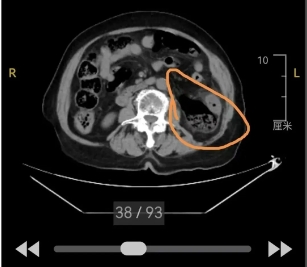

经腹部CT检查提示肠梗阻,外一科韩传学主任会诊后考虑为急性肠梗阻、结肠坏死,不能完全排除肠穿孔可能,已具备急诊手术探查指征!但老人年龄已94岁,身体各器官功能不全,尤其是心肺功能和肾功能均存在不同程度衰竭表现,保守治疗的结局最终是失去生命,手术是唯一的希望!与家属沟通后,家属与医师统一战线,毅然选择背水一战!

14时手术开始,真相远超预期......术中发现乙状结肠粪块性梗阻,近端降结肠水肿、局部缺血表现,肠管脏面观无明显破损表现,腹腔无明显渗液及粪水,游离侧腹膜后发现大量粪水溢出,肠壁穿孔并大面积坏死,左侧腹壁受炎症波及出现大面积软组织坏死,证实为罕见的结肠后壁穿孔、肠坏死、腹壁坏死性筋膜炎!